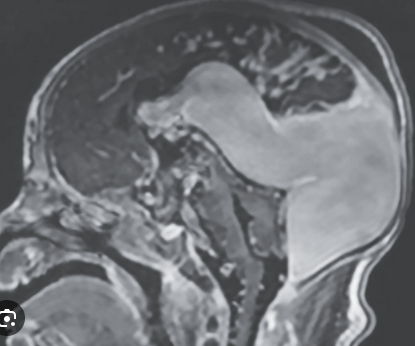

A term female has respiratory failure and the above brain MRI findings.

Describe the MRI finding. Identify the gene responsible.

What is periventricular nodular heterotopia?

What is FLNA gene / FLNA deficiency?

X-linked

Can include a spectrum of other manifestations (CV, pulmonary, GI, joint, platelets)